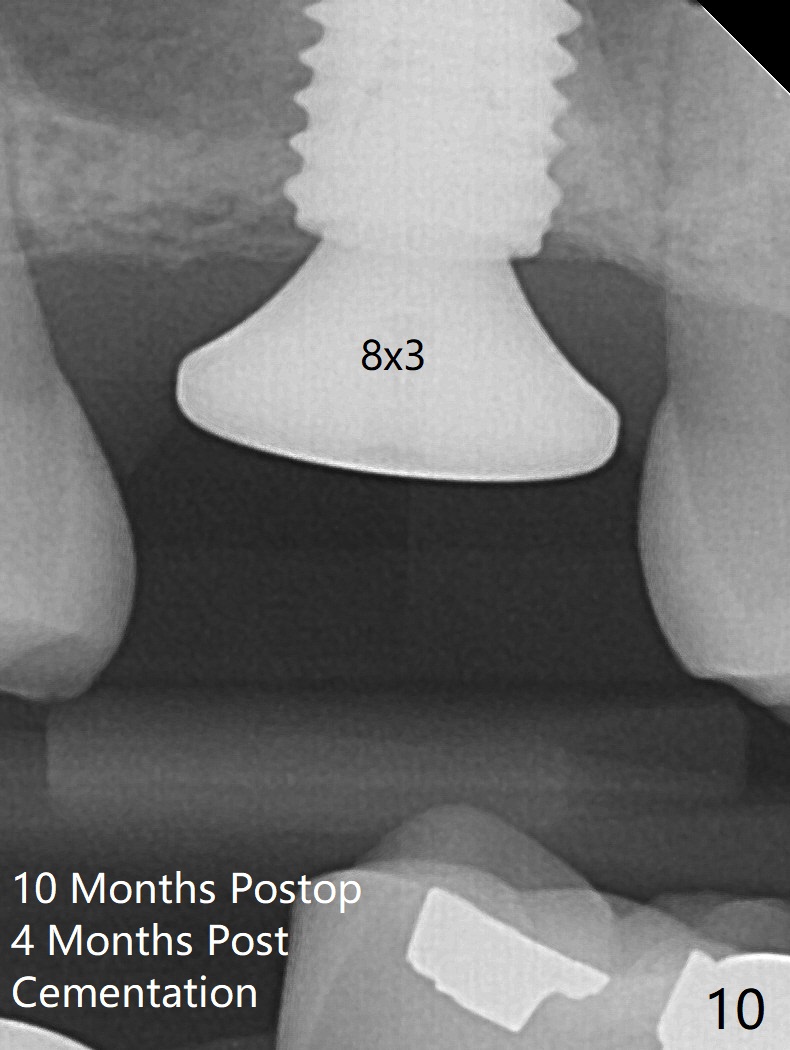

When the residual roots of the tooth #3 are removed, there is a gingival band over the septum (Fig.1 S). Osteotomy (Fig.2 yellow circle) would tear it off. To save the soft tissue, the buccal attachment is severed (Fig.3 black line), the flap is rotated palatal (Fig.3 curved arrow) and sutured in place (Fig.5 S). After sinus floor breakdown (use of sinus drill for 16 mm) and use of membrane lifter/water, two pieces of PRF membrane are inserted. The membrane is so slippery that it is easy to enter the sinus for further sinus membrane lift and later allograft placement (Fig.4 *). A 4.5x10 mm dummy implant is placed with high torque after 4x7.3 mm drill with 3 mm stopper so that 4.5x7.3 mm drill with 1 mm stopper is used before placement of a 5x8.5 mm final implant with ~ 35 Ncm (Fig.5-7). The patient reports anterior sinus wall tenderness with right nasal discharge a few days postop. The provisional has mobility without tenderness 1 week postop. It appears that the sinus membrane has been involved, which is quickly repaired probably by PRF. There is no pain when a 5.2x4(2) mm cemented abutment is torqued at 30-35 Ncm before impression (Fig.8). The surrounding soft tissue is healthy. When the permanent crown is delivered, the patient feels light pain when she bites hard. The discomfort persists 4 months post cementation (Fig.9). The crown/abutment is replaced with a healing abutment (Fig.10). There is no bone loss 4 months post healing abutment placement (14 months post implant placement, Fig.11). Upper Molar Immediate Implant, Prevent Molar Periimplantitis (Protocols, Table), Trajectory II, 31 Flap Not Transferred Xin Wei, DDS, PhD, MS 1st edition 07/26/2019, last revision 10/05/2020